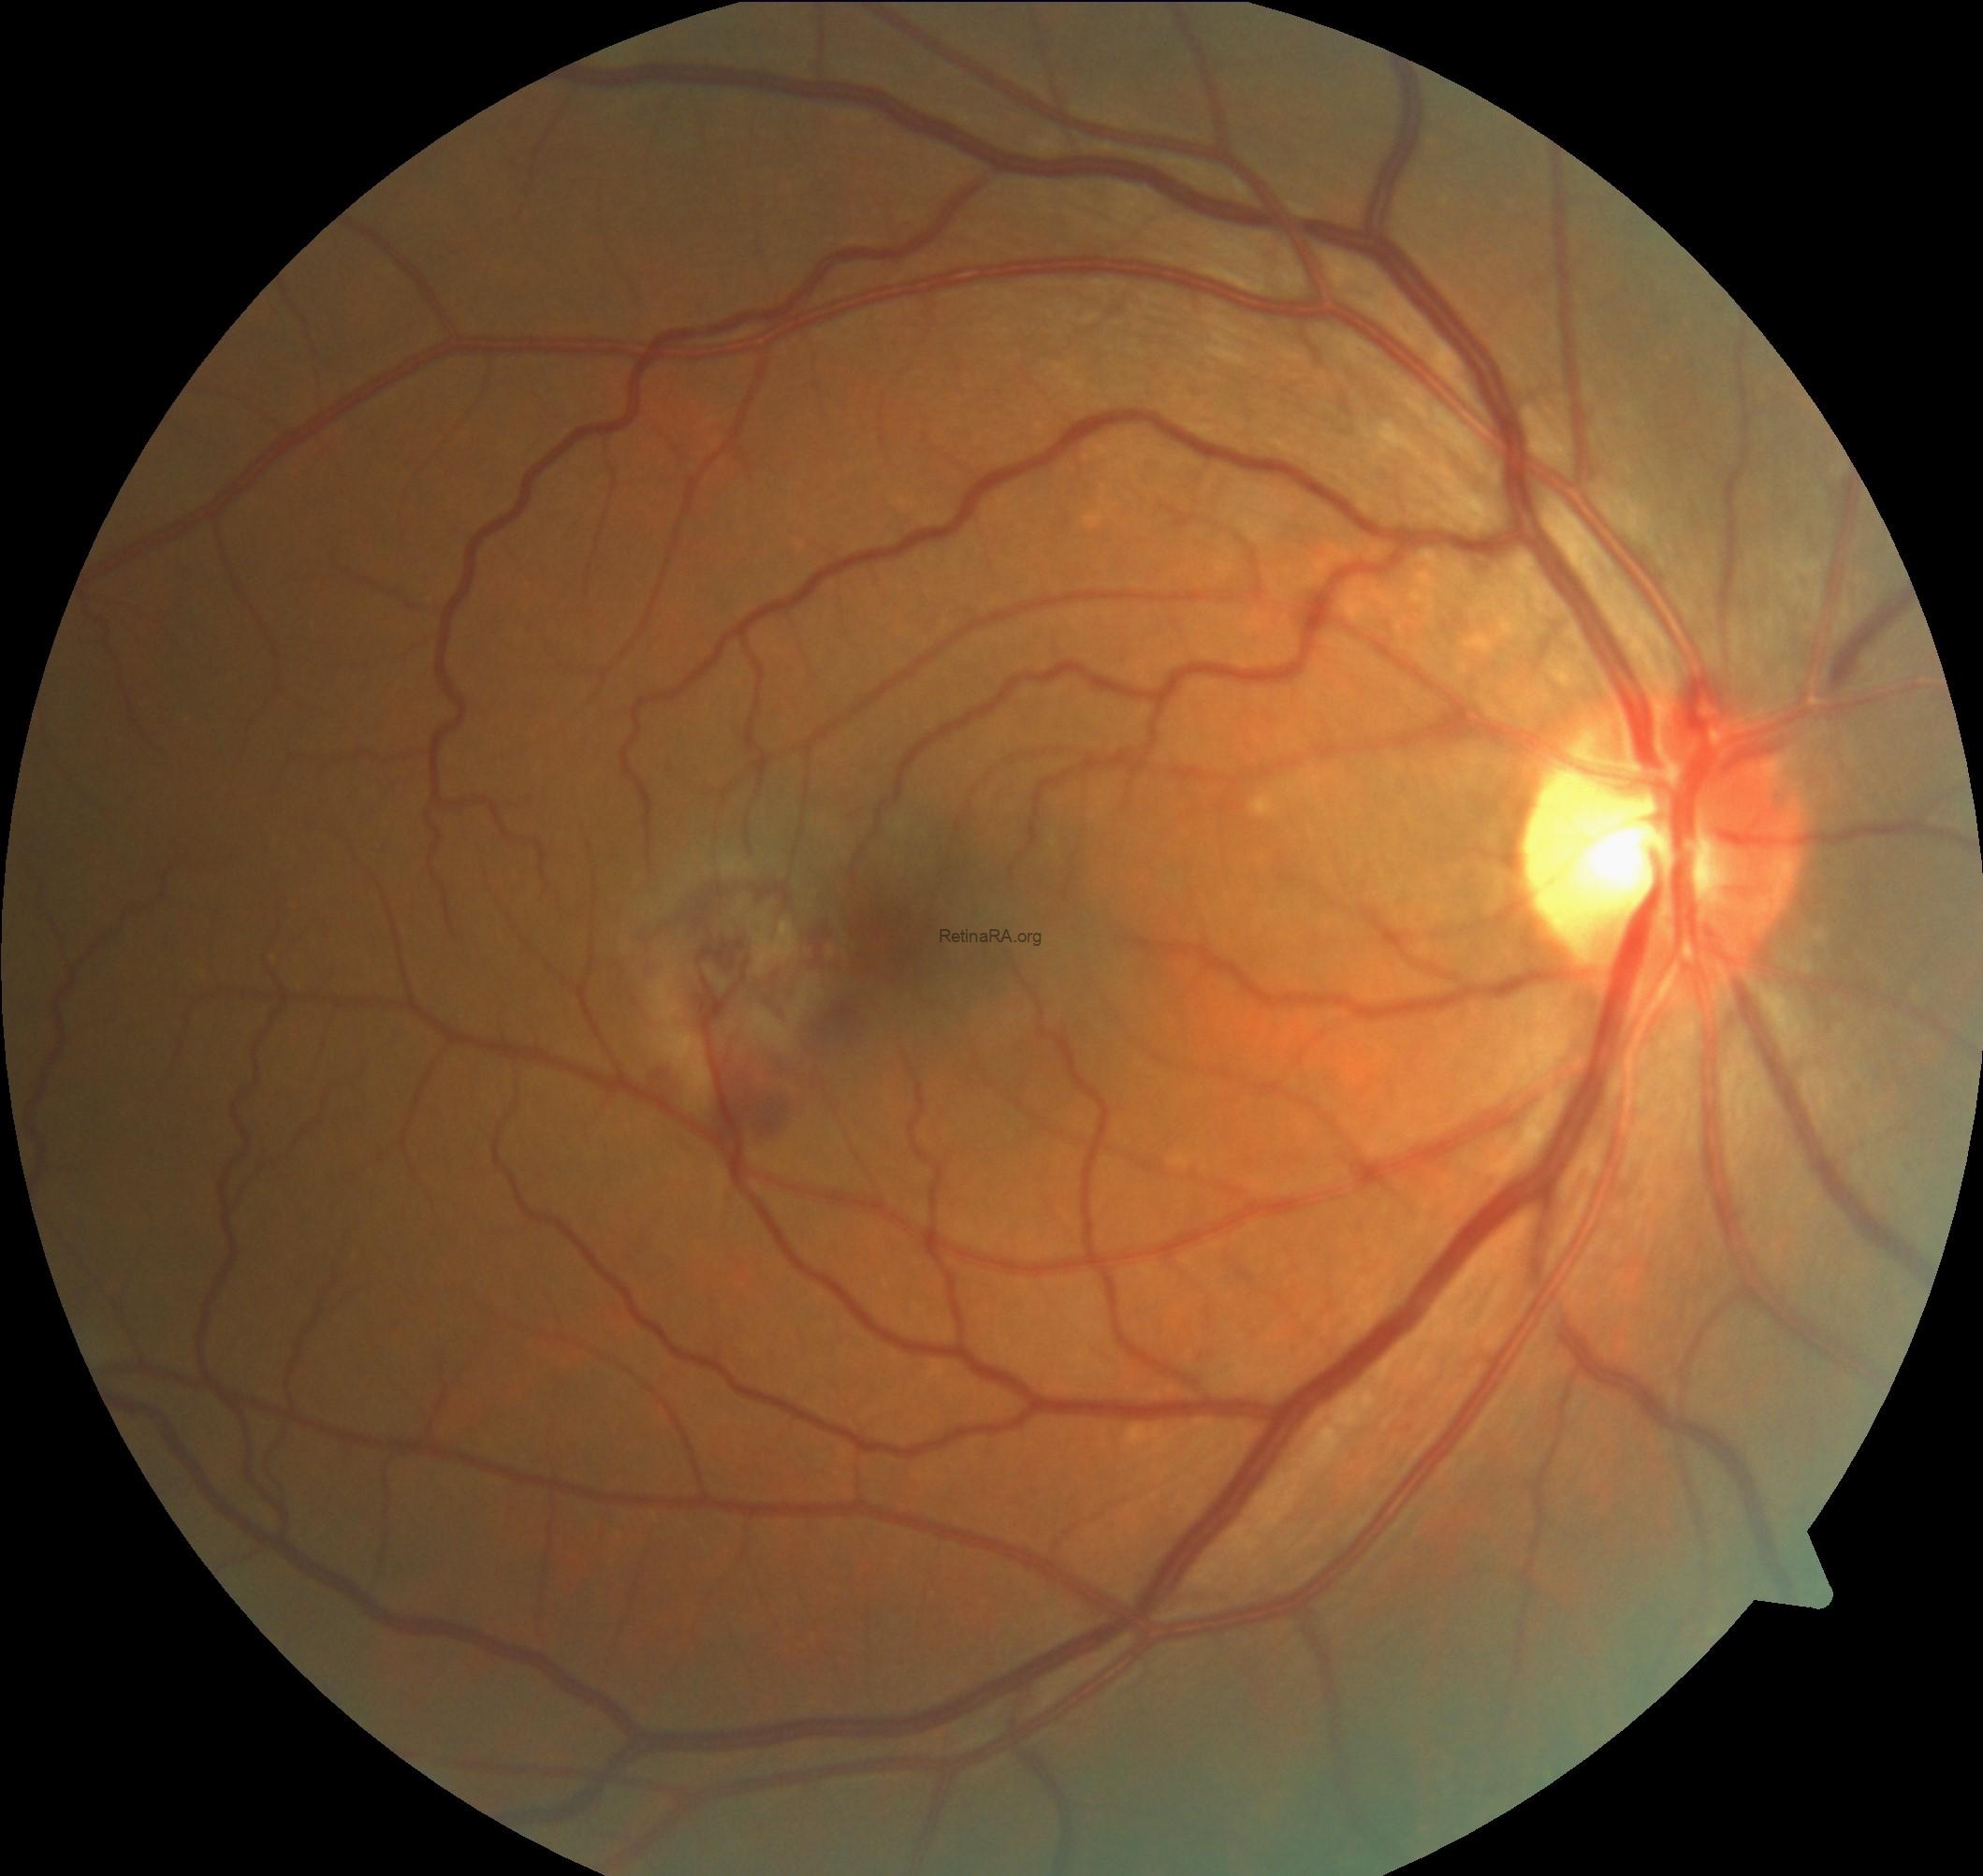

Color fundus photography demonstrated pigmentary alterations temporal to the fovea, along with ectatic capillaries and whitish crystalline deposits. Both eyes showed parafoveal loss of retinal transparency with right-angled venules and telangiectatic vessels, more prominent in the temporal macula. Henle fiber layer hemorrhage appeared in the left eye.

Fundus autofluorescence imaging demonstrated increased parafoveal autofluorescence, most prominently involving the temporal macula, reflecting loss of macular pigment and underlying Müller cell dysfunction. This hyperautofluorescent pattern may become irregular or patchy. Areas corresponding to choroidal neovascularization, subretinal hemorrhage, fibrosis, or retinal pigment epithelium damage appear as focal zones of reduced autofluorescence.

Macular telangiectasia type 2 (MacTel type 2) is a bilateral, neurodegenerative retinal disorder characterized by parafoveal capillary abnormalities and progressive retinal structural changes, which may be complicated by secondary subretinal neovascularization in advanced stages. In the neovascular form, multimodal imaging reveals distinct and complementary findings. Fundus examination may show parafoveal graying, right-angled venules, crystalline deposits, and signs of subretinal neovascular tissue or hemorrhage. Fundus autofluorescence typically demonstrates increased parafoveal autofluorescence, reflecting macular pigment depletion, with superimposed areas of reduced autofluorescence corresponding to neovascular scarring or hemorrhage. Spectral-domain OCT shows inner and outer retinal cavitations, disruption of the ellipsoid zone, retinal thinning, and in neovascular cases, hyperreflective subretinal material associated with subretinal or intraretinal fluid. OCT angiography plays a pivotal role by revealing telangiectatic vascular changes in the superficial and deep capillary plexuses, with neovascular networks often originating from the deep plexus and extending into the outer retinal and avascular slabs. Together, these imaging features support the diagnosis, help differentiate MacTel type 2 from other macular neovascular entities, and guide monitoring and treatment response following anti-VEGF therapy.